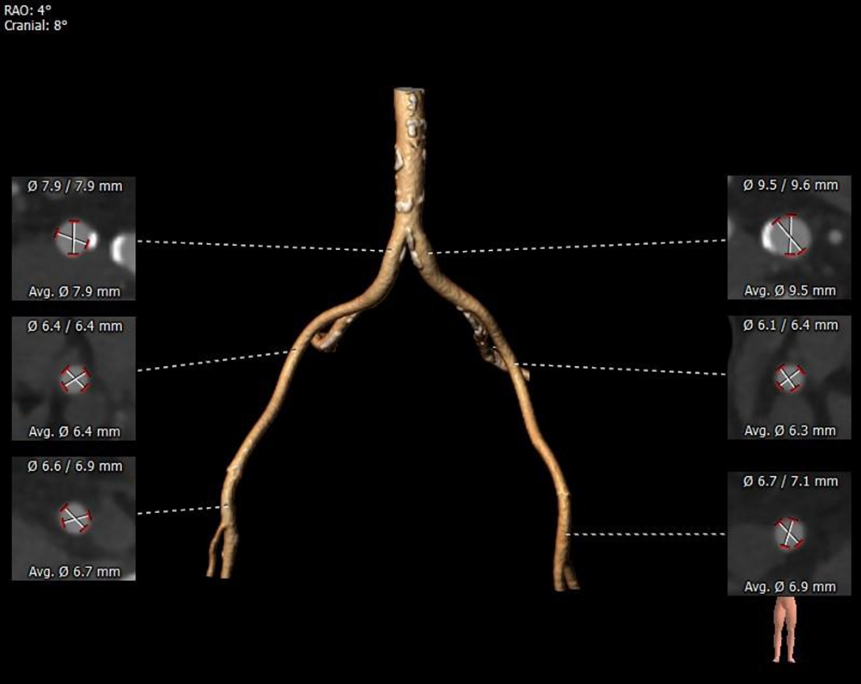

外周血管及主动脉弓解剖

双侧髂总动脉条状钙化,附着斑块,局部管径较细。双侧股髂动脉未见明显扭曲,股动脉穿刺区域内径尚可双。

双侧股动脉管径稍细,髂总动脉条状钙化且管径偏小,血管并发症风险增高。

经过临床严谨的评估及充分的讨论,使用右侧股动脉为主入路,20F动脉鞘内芯常规预扩。可不预扩,若预扩推荐使用18mm球囊预扩张。预装载TaurusEliteAV23瓣膜,瓣环下0-2mm偏高位,在RAO21°CAU28°(双窦展开)下释放。